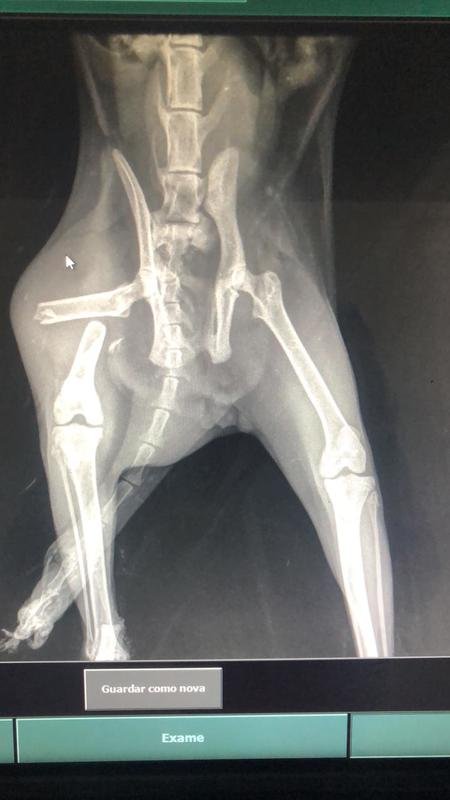

medusa minha gatinha foi atropelada na sexta e largada na rua , e por conta disso está precisando passar por 3 cirurgias, tem duas fraturas no corpo e terá de amputar o rabo. Com todos os gastos, as cirurgias ficaram mais de 3,500 reais, então, precisamos de ajuda para salvarmos ela dessa dor !!